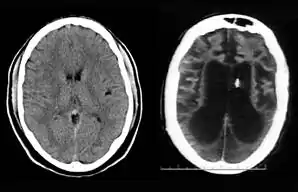

On August 10, 2001, on remand from the Florida Second District Court of Appeal, Judge Greer heard a motion from the Schindlers claiming that new medical treatment could restore sufficient cognitive ability such that Terri Schiavo herself would be able to decide to continue life-prolonging measures. The court also heard motions from the Schindlers to remove the guardian (Michael Schiavo) and to require Judge Greer to recuse himself. Judge Greer denied the motions and the Schindlers appealed to the Second District Court of Appeals. On October 17, 2001, the Court of Appeal affirmed the denials of the motions to remove and recuse. The Court of Appeals acknowledged that their opinion misled the trial court, and they remanded the question of Terri Schiavo's wishes back to the trial court and required an evidentiary hearing to be held. The court specified that five board certified neurologists were to testify. The Schindlers were allowed to choose two doctors to present findings at an evidentiary hearing while Schiavo could introduce two rebuttal experts. Finally, the trial court itself would appoint a new independent physician to examine and evaluate Terri Schiavo's condition. (These decisions, all published in a single order by the Florida Second District Court of Appeal,[34] came to be known by the court as Schiavo III in its later rulings.) In October 2002, on remand by the Second District Court of Appeal, an evidentiary hearing was held in Judge Greer's court to determine whether new therapy treatments could help Terri Schiavo restore any cognitive function. In preparation for the trial, a new computed axial tomography scan (CAT scan) was performed, which showed severe cerebral atrophy. An EEG showed no measurable brain activity. The five physicians chosen were William Maxfield, a radiologist, and four neurologists: William Hammesfahr, Ronald Cranford, Melvin Greer and Peter Bambakidis.[35]

The five doctors examined Terri Schiavo's medical records, brain scans, the videos, and Terri herself. Cranford, Greer, and Bambakidis testified that Terri Schiavo was in a persistent vegetative state (PVS). Drs. Maxfield and Hammesfahr testified that she was in a minimally conscious state. As part of the court-ordered medical exam, six hours of video of Terri Schiavo were taped and filed at the Pinellas County courthouse. The tape included Terri Schiavo with her mother and neurologist William Hammesfahr. The entire tape was viewed by Judge Greer, who wrote, Terri "clearly does not consistently respond to her mother". From that six hours of video, the Schindlers and their supporters produced six video clips intended to support their case, totaling less than six minutes, and released those clips to public websites.[1] Judge Greer ruled that Terri Schiavo was in a PVS, and was beyond hope of significant improvement. The trial court order was particularly critical of Hammesfahr's testimony, which claimed positive results in similar cases by use of vasodilation therapy, the success of which is unsupported in the medical literature.[36] This ruling was later affirmed by Florida's Second District Court of Appeal, which stated that "this court has closely examined all of the evidence in the record", and "we have ... carefully observed the video tapes in their entirety." The court concluded that "if we were called upon to review the guardianship court's decision de novo, we would still affirm it." This decision by the Second District Court of Appeals[37] came to be known as Schiavo IV in later rulings.